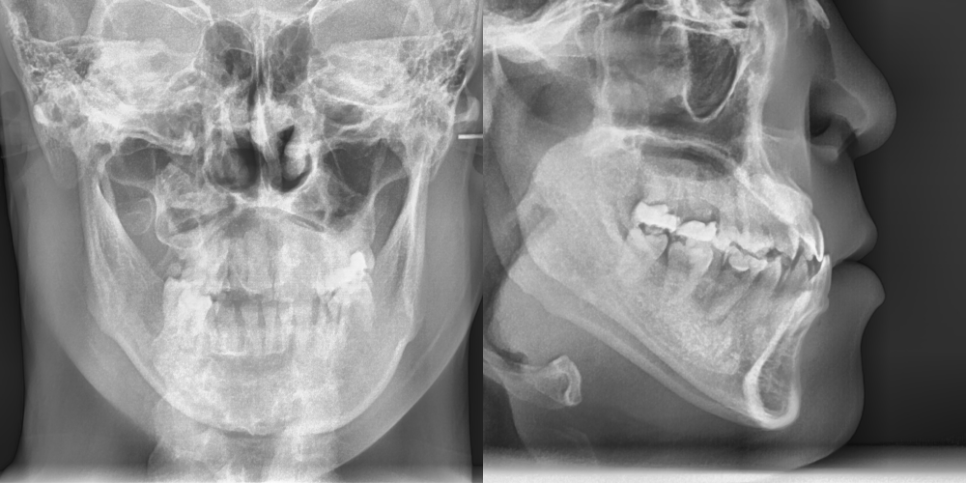

먼저 정밀한 진단과 분석을 통해

골격적 문제와 치아 배열 문제를

구분하여 평가합니다.

23.09.01

3차원 영상 분석과 모델 분석을 통해

치료 계획을 수립하게 되어요.